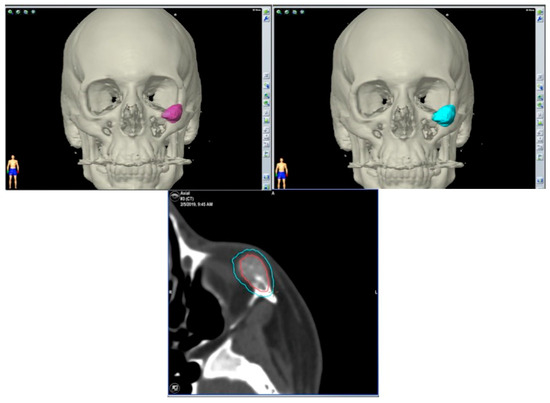

2.3.3. Surgical Navigation

| 3 | 36/F | L/19 mm | Y | 6 mo | N | N | CT, MRI | Zygoma | Arteriovenous malformation | - | Resection + reconstruction | Y | Y | 1st, 2nd, 3rd | Transconjunctival + blepharoplasty + maxillary vestibular | Y | Piezoelectric device | N | PEEK prosthesis | 5 y/N |

| 4 | 47/M | L/30 mm | N | 2 y | N | N | CT | Zygoma | Intraosseous venous malformation | - | Resection + reconstruction | Y | Y | 1st, 2nd, 3rd | Transconjunctival + lateral canthotomy + maxillary vestibular | Y | Piezoelectric device | N | PEEK prosthesis | 6 y/N |